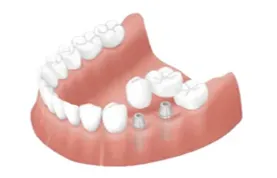

歯の治療には早期発見と早期治療が大切です。歯や神経は生え変わることがないため、今ある自分自身の歯をしっかりと維持し、健康的な状態に保てるように歯科として多角的なサポートをしております。より高精度な治療を行うためにマイクロスコープやエルビウムヤグレーザーなどを導入し、できる限り負担の少ない治療を選択できるように配慮しています。歯の審美性や機能性を向上させる矯正や予防を目的としたホームケアの指導や各種処置、早期発見と早期治療を支える定期検診やメインテナンスなどを湘南台にて実施いたします。

提供している主な治療方法を一覧で掲載しています。お子様からご高齢の方まで、幅広い年代に対応するため、施術方法も多種多様に取り揃えております。